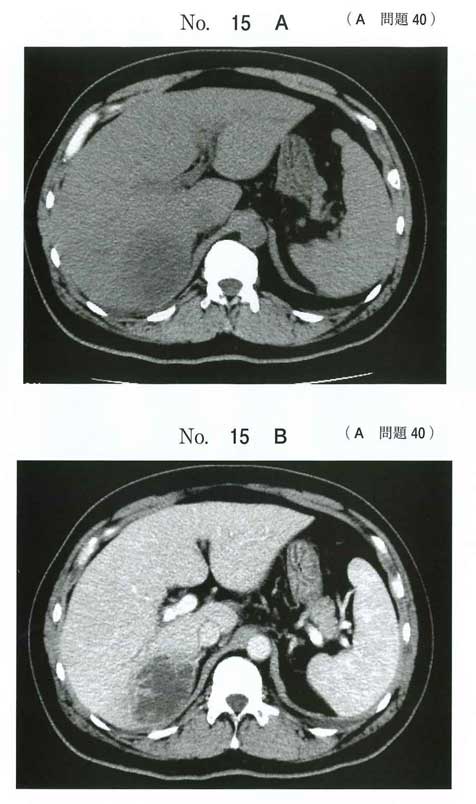

Klebsiella pneumoniaeによる肝膿瘍および眼内炎